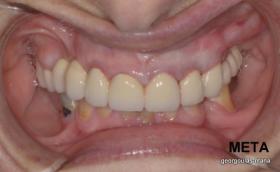

Στην ασθενή αυτή πραγματοποιήθηκε ανοικτή ανύψωση ιγμορείου άνω αριστερά. Σε πρώτη φάση πραγματοποιήθηκε η οστική αύξηση και 6 μήνες μετά τοποθετήθηκαν 3 εμφυτεύματα. Τόσο στην πανοραμική όσο και στην τομογραφία κωνικής δέσμης (CBCT) που πραγματοποιήθηκαν 6 μήνες μετά την ανύψωση είναι εμφανής ο σχηματισμός οστού. Η τελευταία ακτινογραφία και φωτογραφία λήφθηκαν 5 χρόνια μετά την προσθετική αποκατάσταση.